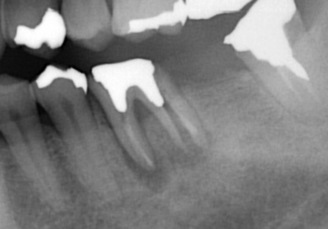

それでは、分かりやすくするために赤丸の部分を拡大してみます。

奥の根が折れているのが分かるかと思います。

このように歯根破折 している場合には、抜歯となります。

通常歯根破折 していてもこのようにレントゲンではっきりと写ることは少ないのです。